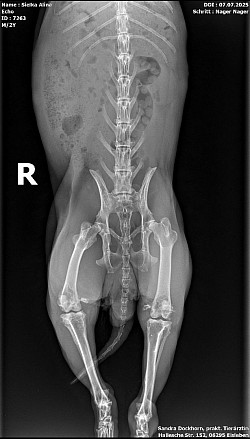

Röntgenbilder

Interressant, oder? Troll sein gebrochener Zeh und Echo seine Kniefraktionen und sein Stufengebiss.

Echo bekommt ein vorbeugenes Mittel gegen Arthrose und kriegt einen Zahnarztbesuch (Leipzig) und Troll wird jetzt bei Dr. Rust im Salzatal vorgestellt.